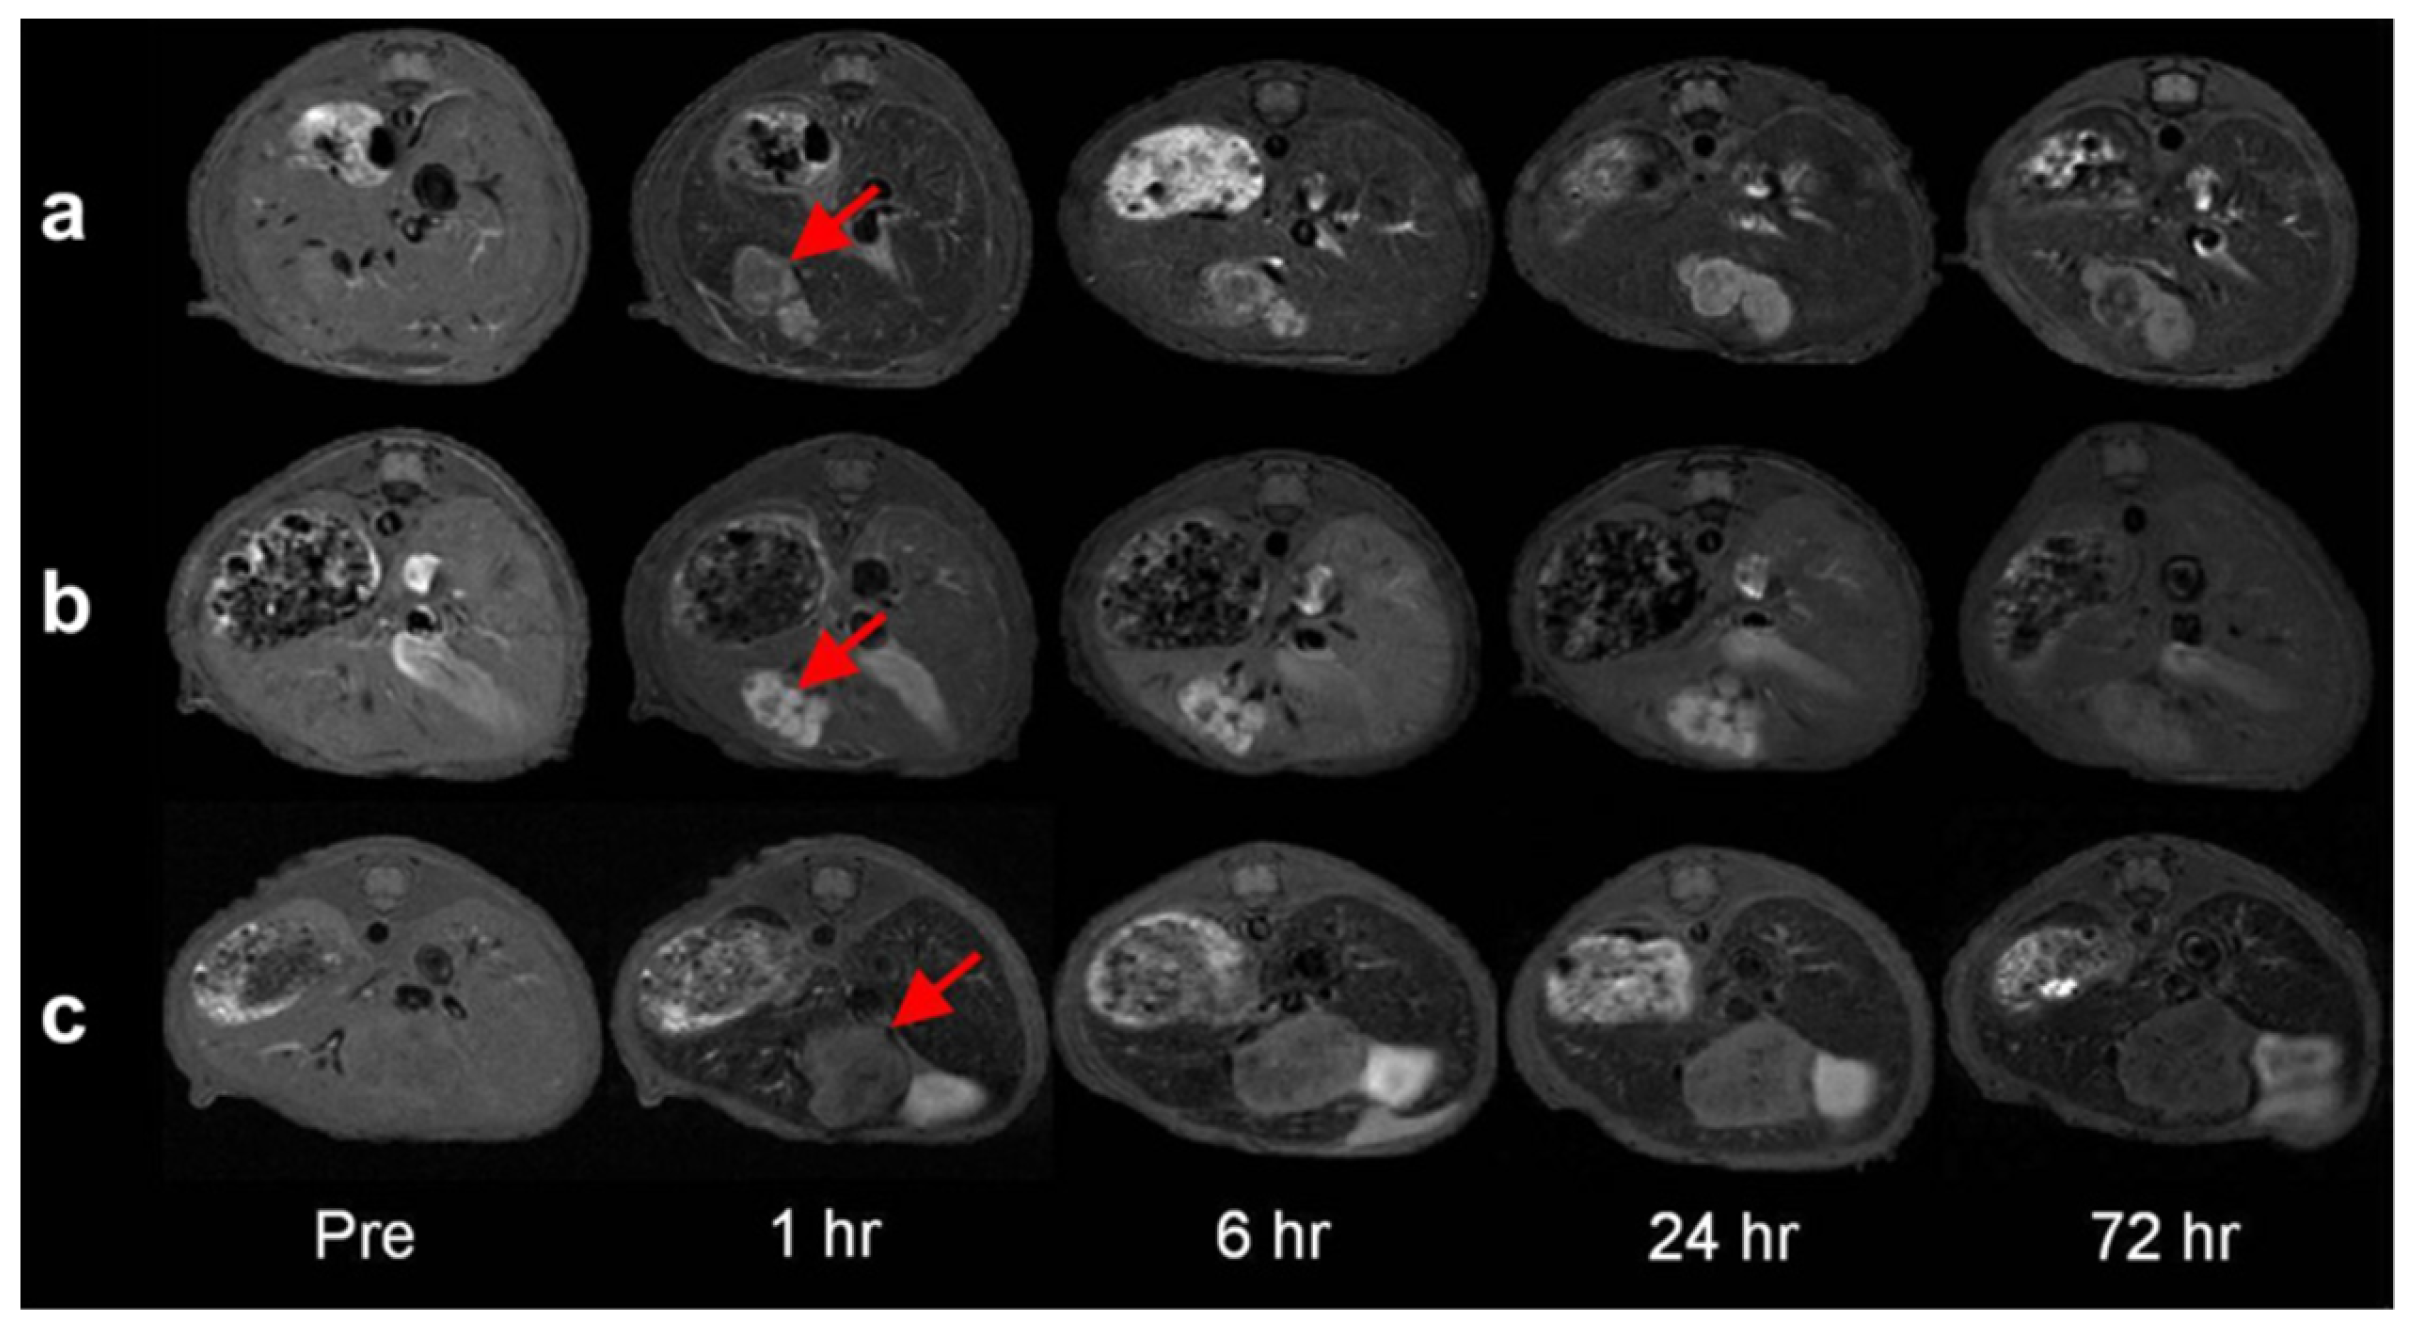

- Shin, T.-H.; Choi, J.-s.; Yun, S.; Kim, I.-S.; Song, H.-T.; Kim, Y.; Park, K.I.; Cheon, J. T1 and T2 dual-mode MRI contrast agent for enhancing accuracy by engineered nanomaterials. ACS Nano 2014, 8, 3393–3401. [Google Scholar] [CrossRef]

| Gd2O3@ Fe3O4-HDA-G2 (GdIO) | 69.5 | 146.5 | 2.1 | 0.5 | 14; -* | In vitro HeLa, HepG2 cells In vivo Balb/c/HepG2 tumor mice (7 T) | [103] |

| Fe3O4 | * | 125.4 | * | 14; -* | |||

| Gd2O3 | 12.1 | * | * | 2; -* | |||